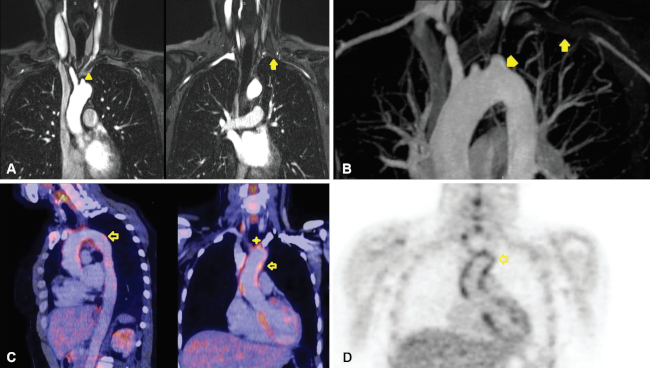

La PET-TC permite una localización anatómica más precisa de la actividad de la enfermedad con aumento de la captación de 18-FDG como marcador de inflamación (►Fig. 2).7,9

Arteritis de células gigantes

La arteritis de células gigantes o arteritis de la temporal es una vasculitis granulomatosa de vasos de mediano y gran calibre que afecta a población mayor a 50 años.10

Compromete principalmente las ramas de la arteria carótida externa, especialmente la temporal superficial, vertebrales, coronarias y la aorta en el 15% de los casos.11

Se encuentra en asociación con la polimialgia reumática (un 60%), que presenta síntomas como rigidez y dolor en la cintura escapular y pelviana, y signos como el aumento de reactantes de fase aguda en análisis de laboratorio.

La TCMD y RM evidencian:

Ectasia

Aneurismas de la porción ascendente que se extienden hacia el cayado

Disección aguda

Insuficiencia valvular aórtica

Aneurismas de la aorta abdominal

Engrosamiento mural circunferencial12

Mediante la utilización de la TCMD, se pueden ver cambios en la pared, como calcificaciones o trombosis, mientras que la RM detecta edema de la pared de los vasos cuando la enfermedad se encuentra activa.13

El principal diagnóstico diferencial desde el punto de vista clínico es con el hematoma intramural (HIM) de origen ateroesclerótico, cuyo engrosamiento mural es parcial y en forma de semiluna (►Fig. 3.).1,14